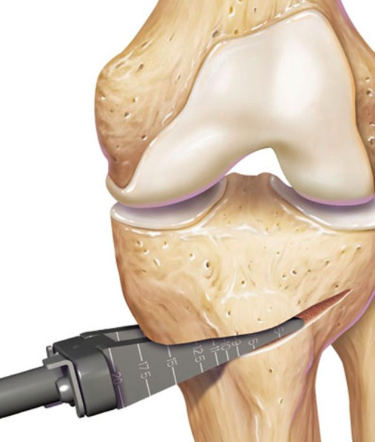

Des ostéotomies sont indiquées s’il y a présence d’un mal alignement articulaire. L’avantage principal de l’ostéotomie est la préservation de l’articulation. Ceci peut permettre de retarder l’arthroplastie, surtout chez les jeunes patients.

L’ostéotomie permet un réalignement osseux, qui aura pour effet de mieux répartir la charge mécanique sur une surface articulaire saine, tout en préservant le stock osseux. On va couper un petit triangle dans l’os pour permettre de choisir ou s’appuiera la charge mécanique

Elle est principalement pratiquée au niveau du tibia proximal dans les arthroses varisantes du genou.